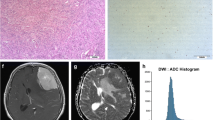

In this retrospective study, we evaluated the distribution of absolute and normalized ADC values of medulloblastomas. Tumors were manually segmented and diffusivity metrics calculated on a pixel-by-pixel basis. We calculated a variety of first-order histogram metrics from the ADC maps, including entropy, minimum, 10th percentile, 90th percentile, maximum, mean, median, skewness and kurtosis, to differentiate molecular and histological variants. ADC values of the tumors were also normalized to the bilateral cerebellar cortex and thalami. We used the Kruskal–Wallis and Mann–Whitney U tests to evaluate differences between the groups. We carried out receiver operating characteristic (ROC) curve analysis to evaluate the areas under the curves and to determine the cut-off values for differentiating tumor groups.

We found 65 children with confirmed histopathological diagnosis of medulloblastoma. Mean age was 8.3 ± 5.8 years, and 60% (n = 39) were male. One child was excluded because histopathological variant could not be determined. In terms of medulloblastoma variants, tumors were classified as classic (n = 47), desmoplastic/nodular (n = 9), large/cell anaplastic (n = 6) or as having extensive nodularity (n = 2). Seven other children were excluded from the study because of incomplete imaging or equivocal molecular diagnosis. Regarding medulloblastoma molecular groups, there were: wingless (WNT) group (n = 7), sonic hedgehog (SHH) group (n = 14) and non-WNT/non-SHH (n = 36). Our results showed significant differences among the molecular groups in terms of the median (P = 0.002), mean (P = 0.003) and 90th percentile (P = 0.002) ADC histogram metrics. No significant differences among the various medulloblastoma histological variants were found.

ADC histogram analysis can be implemented as a complementary tool in the preoperative evaluation of medulloblastoma in children. This technique can provide valuable information for differentiating among medulloblastoma molecular groups. ADC histogram metrics can help predict medulloblastoma molecular classification preoperatively.